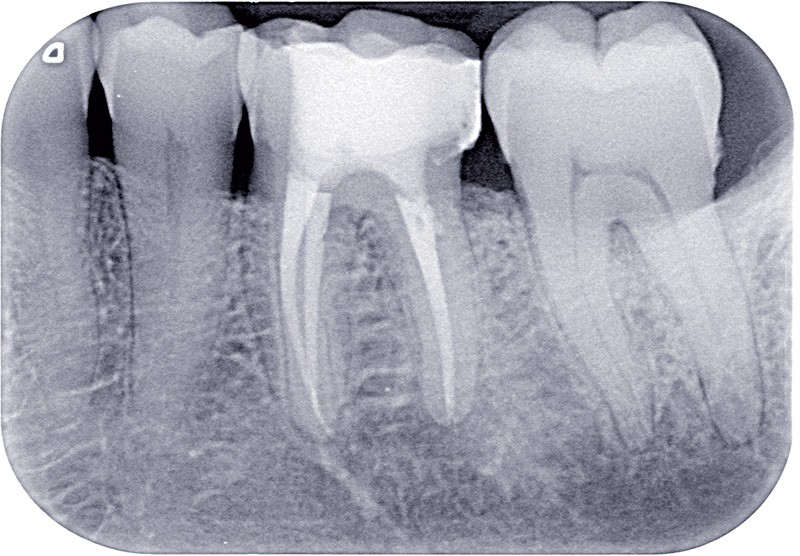

Dans ces situations, le praticien est conduit à dépulper et à restaurer les dents traitées endodontiquement. Les traitements doivent alors s’inscrire dans le concept du continuum endo-restaurateur qui a été défini comme étant « le processus spatio-temporel sans interruption ni rupture qui débute par l’accès à l’endodonte et s’achève avec la mise en place de la restauration prothétique d’usage » (1). Il existe bien une continuité, du traitement endodontique à la restauration fonctionnelle d’usage qui conditionne le pronostic et les résultats du traitement à long terme (fig. 2).

L’obturation tridimensionnelle canalaire permet de maintenir l’état de désinfection obtenu lors de la préparation chimiomécanique. C’est l’obturation complète de l’ensemble du réseau canalaire, aussi près que possible de la jonction cémentodentinaire. Elle fait partie intégrante de la triade endodontique dont les deux autres composantes sont la mise en forme et l’irrigation. Le praticien est amené à se poser la question suivante : quelle technique d’obturation choisir ? La vraie problématique réside dans la mise en forme. En effet, un canal mal mis en forme sera mal nettoyé et par conséquent mal obturé. Ainsi, les différents…